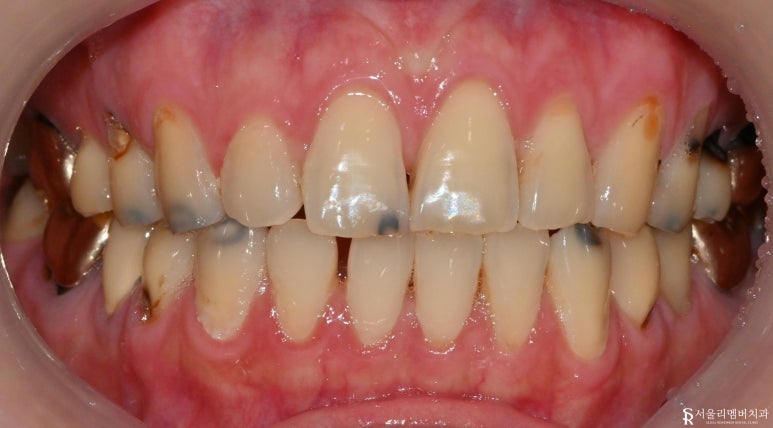

구내사진

곳곳에 심한 충치들을 확인할 수 있습니다.

인레이로 수복치료되어 있던

치아들도 통증이 있다고 하셔서

보철 제거 후 확인합니다.

모두 상태가 악화되어 크라운으로

재치료를 하는 것이 좋겠습니다.

충치 부위를 삭제하고 치료 들어가 보겠습니다.